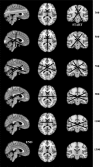

Current advances in neurosciences deal with the functional architecture of the central nervous system, paving the way for general theories that improve our understanding of brain activity. From topology, a strong concept comes into play in understanding brain functions, namely, the 4D space of a "hypersphere's torus", undetectable by observers living in a 3D world. The torus may be compared with a video game with biplanes in aerial combat: when a biplane flies off one edge of gaming display, it does not crash but rather it comes back from the opposite edge of the screen. Our thoughts exhibit similar behaviour, i.e. the unique ability to connect past, present and future events in a single, coherent picture as if we were allowed to watch the three screens of past-present-future "glued" together in a mental kaleidoscope. Here we hypothesize that brain functions are embedded in a imperceptible fourth spatial dimension and propose a method to empirically assess its presence. Neuroimaging fMRI series can be evaluated, looking for the topological hallmark of the presence of a fourth dimension. Indeed, there is a typical feature which reveal the existence of a functional hypersphere: the simultaneous activation of areas opposite each other on the 3D cortical surface. Our suggestion-substantiated by recent findings-that brain activity takes place on a closed, donut-like trajectory helps to solve long-standing mysteries concerning our psychological activities, such as mind-wandering, memory retrieval, consciousness and dreaming state.